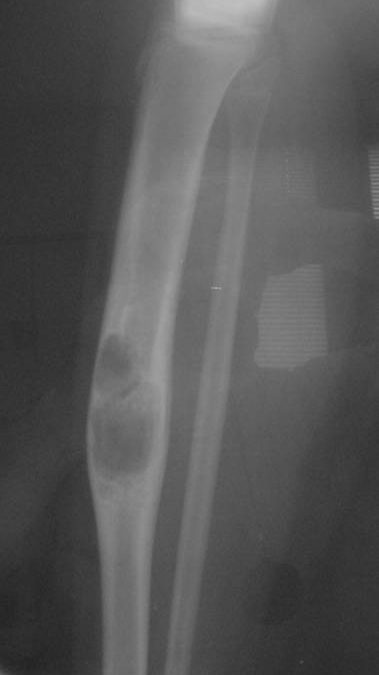

An aneurysmal bone cyst develops when abnormal blood flow within the bone leads to the formation of multiple blood-filled spaces. These cavities expand and weaken the bone from the inside, creating a balloon-like appearance on imaging studies.

Diagnosis begins with imaging tests such as X-rays, MRI, or CT scans, which can show the characteristic “soap-bubble” appearance of an ABC. However, because other conditions can appear similar, a biopsy is typically performed to confirm the diagnosis and rule out more serious tumors.